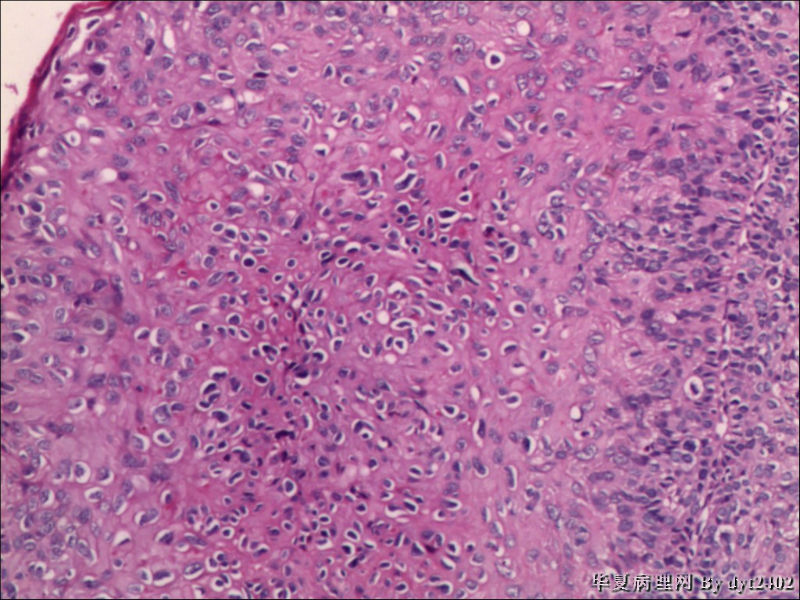

• 宫颈活检 其中一点较迷糊图1

图1

四点中三点是CIN iii,另一点怀疑有更重病变

这个病人是44岁,去年11月底阴道脱落细胞、TCT均见细胞异常,建议活检,病人犹豫,接着单位组织到外院体检时做阴道镜正常,后霉菌感染,此时宫颈未涂醋肉眼看还光滑,直至今年3月来做活检,事前做白带检查又见异常细胞,宫颈未涂醋见后上唇白上皮,涂醋酸后上下唇都有厚白上皮,镶嵌,夹活时上皮剥脱,未能夹到间质,阴道镜医生说至少有CIN III 到原位癌了。。镜下其中3点CIN III无疑,唯有9点处如6、7、11、14等所示结构,但我未见间质浸润,不能说是浸润癌,不知道有没基底细胞样鳞癌的可能,我发了个原位癌不除外深部有更重病变,。